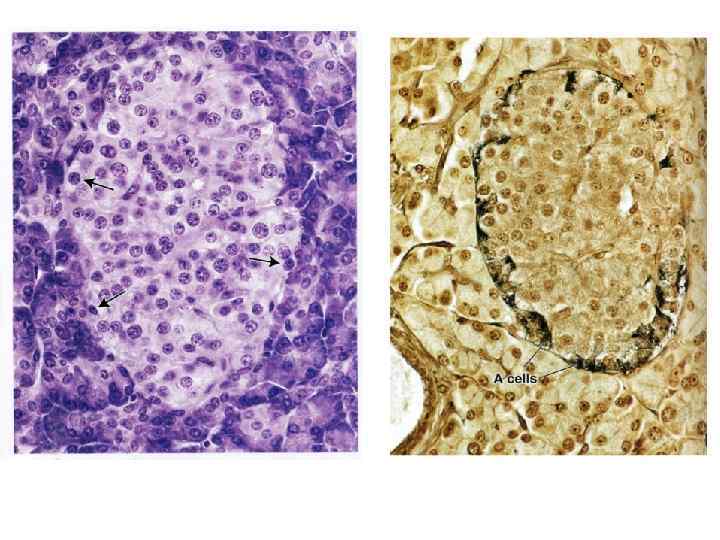

Панкреатический островок А клетки – глюкагон В-клетки – инсулин D-клетки – соматостатин D 1 -клетки – вазоактивный интестинальный пептид РР-клетки - панкреатический полипептид